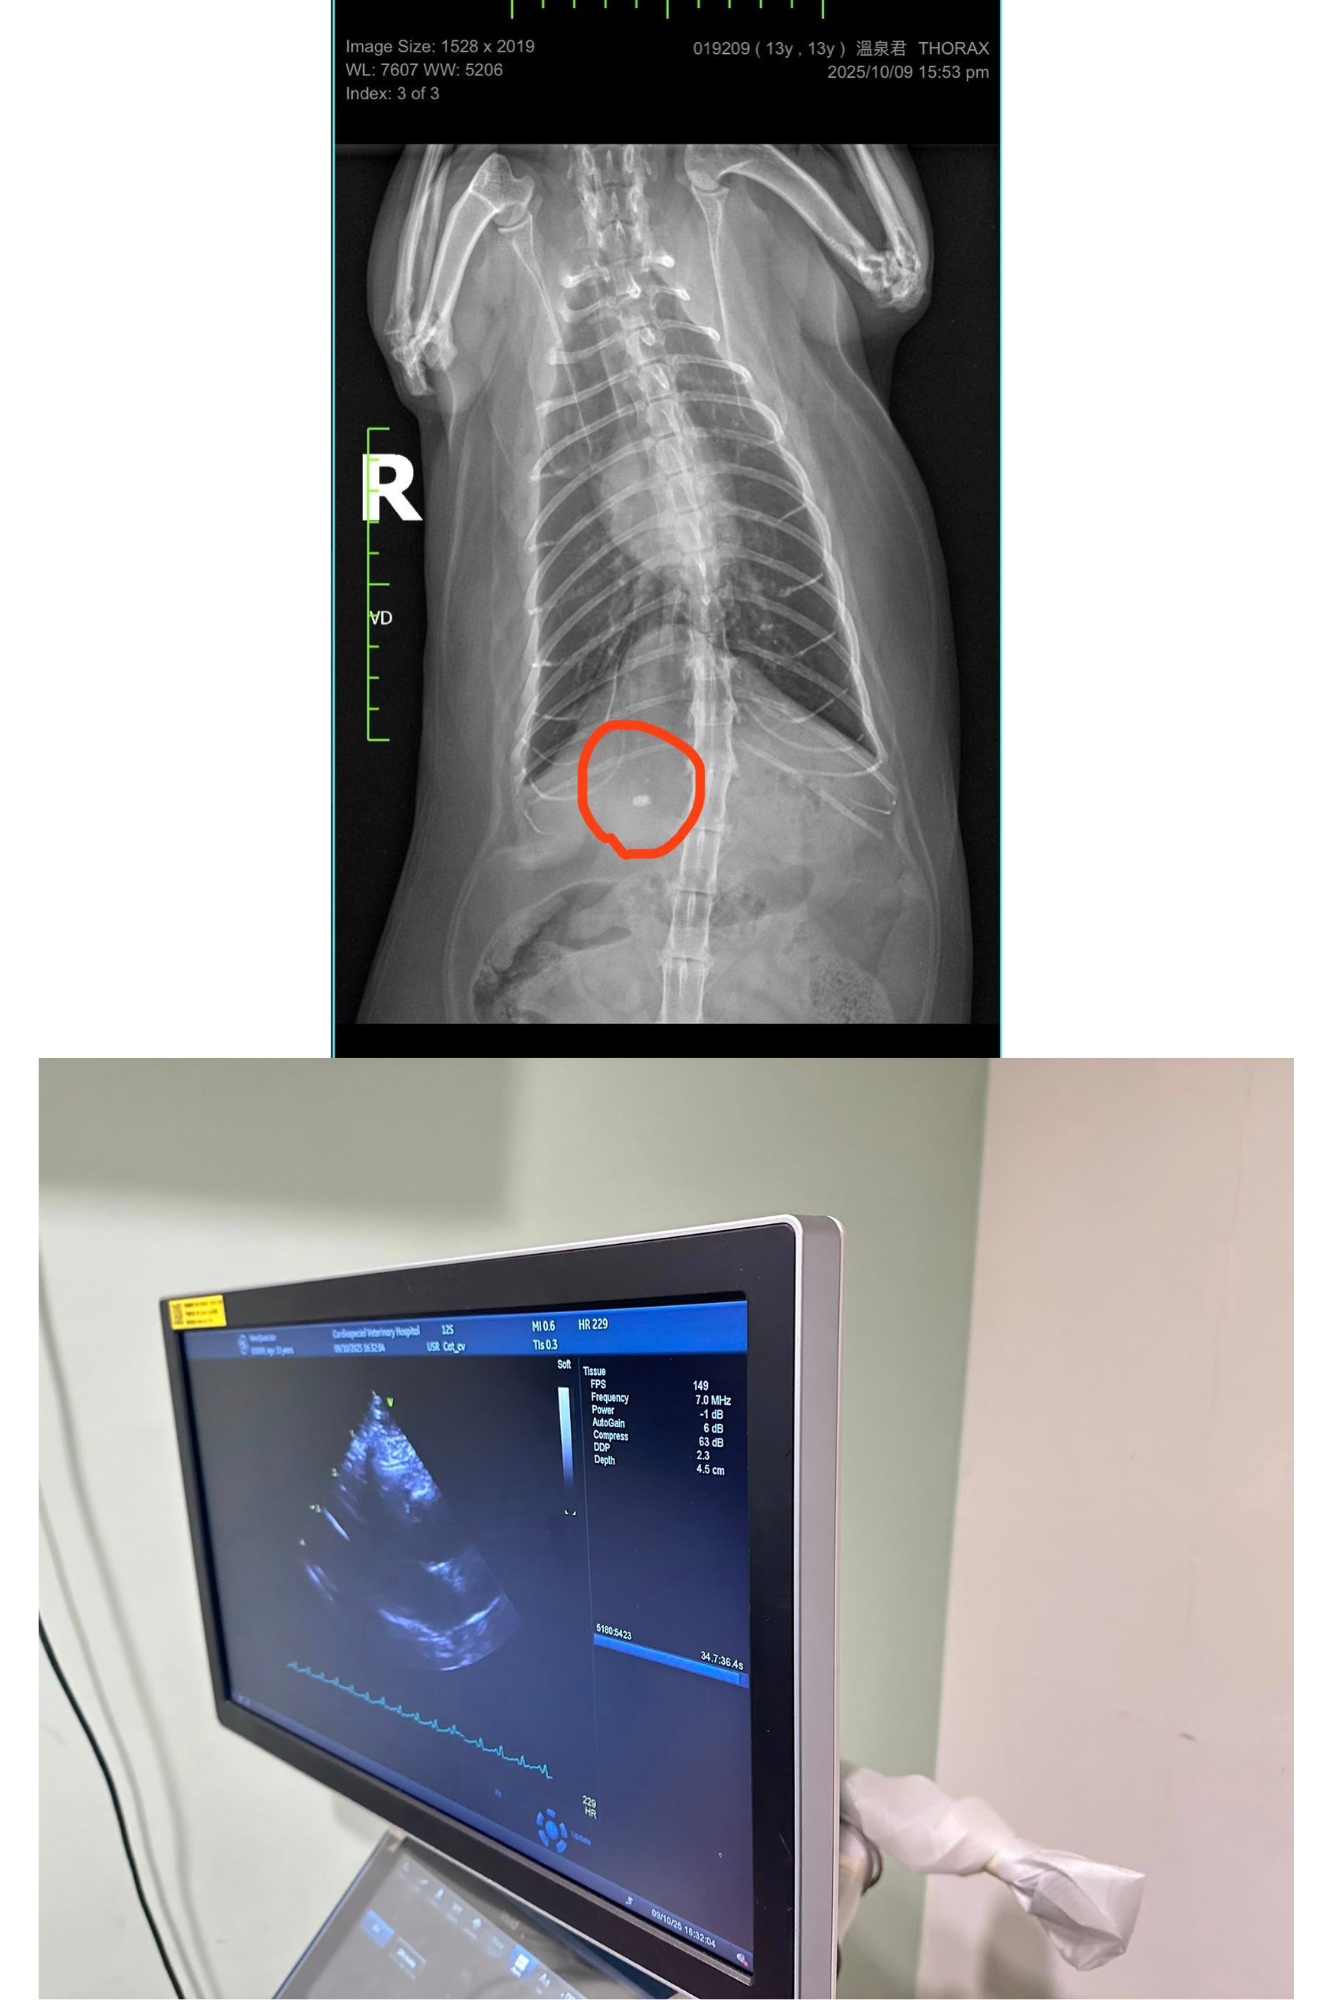

2025年10月9日誌專心醫院進行心臟檢查,今日主要做心臟的X光、超音波檢查、心電圖檢測。血壓正常無明顯心雜音。胸腔X光發現心臟輪廓大小正常,未見肺積水或胸膜積液證據。

右前腹腔影像有一礦物化物質,疑似膽結石,不確定是皮下或腹腔內,但需詳細確認的話,需用超音波檢測。總體來說,溫泉君心臟維持的不錯,無惡化。平時請密切監控心跳與呼吸,請避免過度興奮緊張與任何明顯加快心跳的理由。

今日主要做心臟的X光、超音波檢查、心電圖檢測。

血壓正常120-130,無明顯心雜音。

胸腔X光發現心臟輪廓大小正常,未見肺積水或胸膜積液證據。

右前腹腔影像有一礦物化物質,疑似膽結石,不確定是皮下或腹腔內。

但需詳細確認的話,需用超音波檢測。

心臟超音波發現左心房大小與三年前相比,一樣是肥厚心肌病,但無明顯變大。屬於B1期。

心電圖的部分,沒有傳導的異常,心跳檢測時有因緊張過快,但並沒有早跳停拍的狀況。

醫師另外建議溫泉君可追蹤甲狀腺濃度的變化。

總體來說,溫泉君心臟維持的不錯,無惡化。

平時請密切監控心跳與呼吸,請避免過度興奮緊張與任何明顯加快心跳的理由。